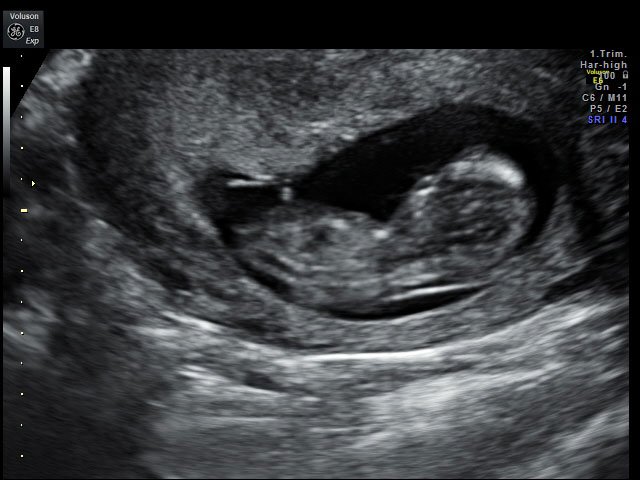

Έμβρυο 12 εβδομάδων με κυφοσκολίωση

Η κυφοσκολίωση εμβρύου αποτελεί σπάνια ανωμαλία που σχετίζεται με βλάβη της σπονδυλικής στήλης και συνυπάρχει επίσης απουσία μέρους η ολόκληρου σπόνδυλου καθώς και πολλές φορές είναι ανωμαλία μη βιώσιμη με τη ζωή. Μπορεί να συνδυαστεί με μικρομελία ή νανισμό, σπάνια σύνδρομα όπως αχονδρογένεση 2.

Στην περίπτωση όπου η ανωμαλία σοβαρού βαθμού κυφοσκολίωσης είναι συμβατή με τη ζωή και διαγιγνώσκεται νωρίς στον τρίτο μήνα το νεογνό, το παιδί θα έχει σοβαρό πρόβλημα κινητικότητας των κάτω άκρων.